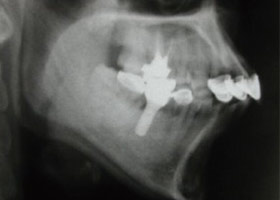

1. 術前口內正面照、局部X光片。

2. 上顎明顯暴牙、下顎參差不齊。

3. 矯正前,明顯可見暴牙。